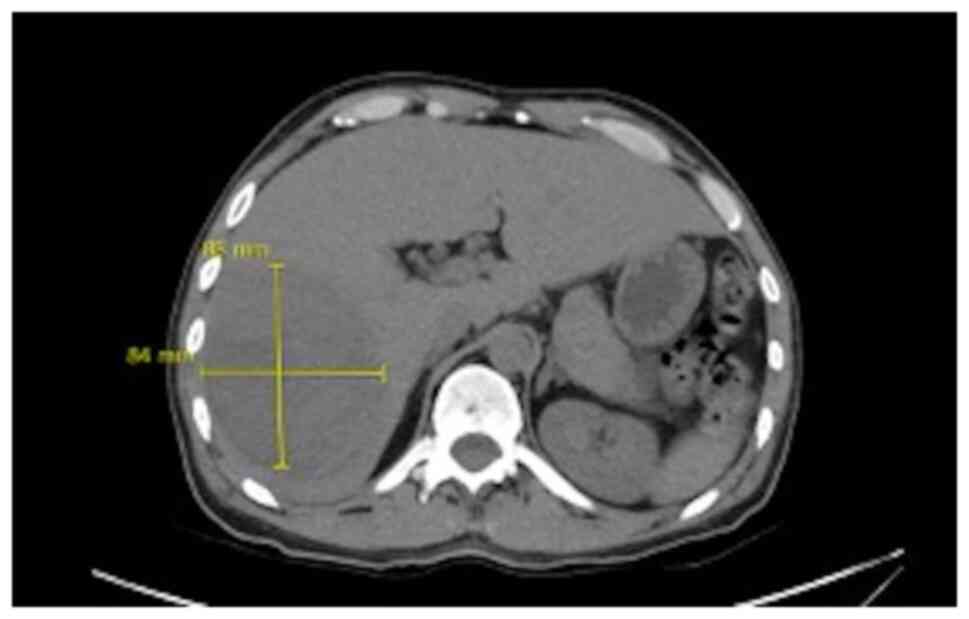

It was decided to perform PoCUS (LOGIQ e, GE Healthcare) following previously established protocols (6). A hypodense intrahepatic image was observed between segments VII and VI, with internal echoes suggestive of a liver abscess (Fig. 1). An ultrasound of the liver and bile ducts performed by a radiologist was requested. A well-defined hypodense lesion between segments VII and VI was confirmed, measuring 81x78x76 mm, with an approximate volume of 253 cc. He presented internal echoes, faint posterior acoustic enhancement and minimal perilesional vascular flow, findings that were associated with the clinical suspicion of liver abscess (Fig. 2). On the same day, radiology and general surgery were consulted. It was decided to perform tomography-guided percutaneous drainage of the liver abscess (IQon Spectral CT, Philips) following formerly recognized protocols (6). A 230 cc drainage was obtained, with no complications (Fig. 3, Fig. 4 and Fig. 5).

Figure 3

Simple abdominal tomography. Evidence of liver injury in segments VI and VII is compatible with an 84x88 mm abscess.